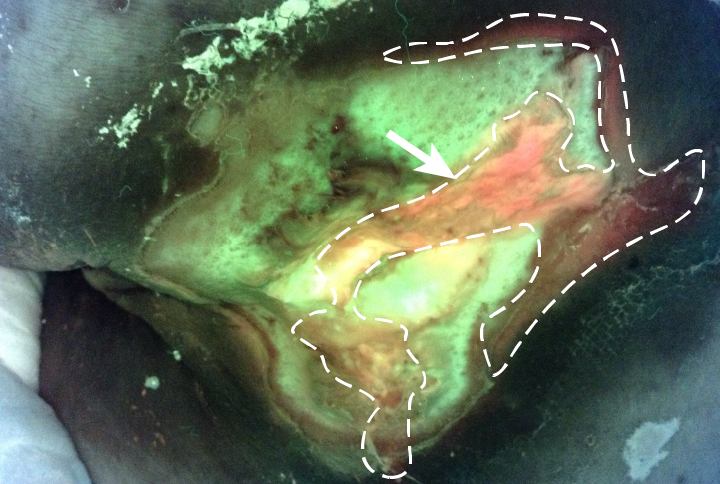

October 11, 2018 -Figure 4: FL-image Bacteria appear red/blush pink in image Read More

October 11, 2018 -Figure 2: FL-image Bacteria appear red/blush pink in image Read More